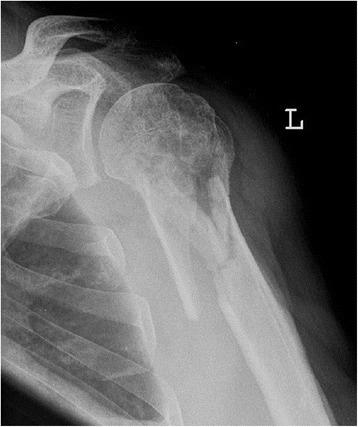

The ideal method for the surgical treatment of proximal humeral fractures has not yet been found. We therefore conducted a retrospective matched-pair analysis and compared osteosynthesis with open reduction and internal fixation and that with an angular stable plate with minimally invasive, closed reduction, percutaneous fixation with the Humerusblock.

During a study period of 3 years, we matched 30 patients treated with angular stable plates (group 1) for age, gender, fracture type and handedness (dominant or nondominant) to 30 patients treated using the Humerusblock (group 2). At a minimal follow-up of 24 months, clinical evaluation included the Constant-Murley score, the UCLA score and the Simple Shoulder Test. Subjective pain was evaluated using the VAS pain scale. Patients were asked to rate their subjective satisfaction of final outcome as excellent, good, satisfied or dissatisfied.

The mean CMS, UCLA score and SST differed significantly between groups 1 and 2 (60.9 vs 71.9, p < 0.01), (25.1 vs 29.5, p < 0.01) and (8.1 vs 9.4, p < 0.05), respectively. The VAS pain score was significantly lower in group 2 than in group 1 (1.2 vs 2.4; p < 0.01). The mean abduction (109.7° vs 133.7°; p < 0.01) and anterior flexion (128.3° vs 145.7°; p < 0.01) were significantly worse in group 1. The mean operation time was significantly shorter in group 2 (117.3 vs 72.1, p < 0.01). Complications occurred in 30 % (group 1) and 23 % (group 2) of patients.

In this study, the functional outcome is superior in the Humerusblock group. However, the general outcome after surgical treatment of 3-and 4-part fractures is moderate, and the complication rate has to be considered, even though it can be lowered with the use of minimally invasive implants.